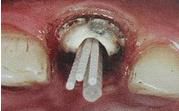

如果是后牙需要打多個纖維樁時要檢查是否互相妨礙以及就位順序等。

一般纖維樁使用數(shù)目要根據(jù)根管的粗細(xì)和牙體缺損范圍來設(shè)計,像牙膠尖根充一樣,在主尖周圍可以放置輔尖。

后牙一般按照牙體缺損范圍來設(shè)計,一般2到4個足夠了。